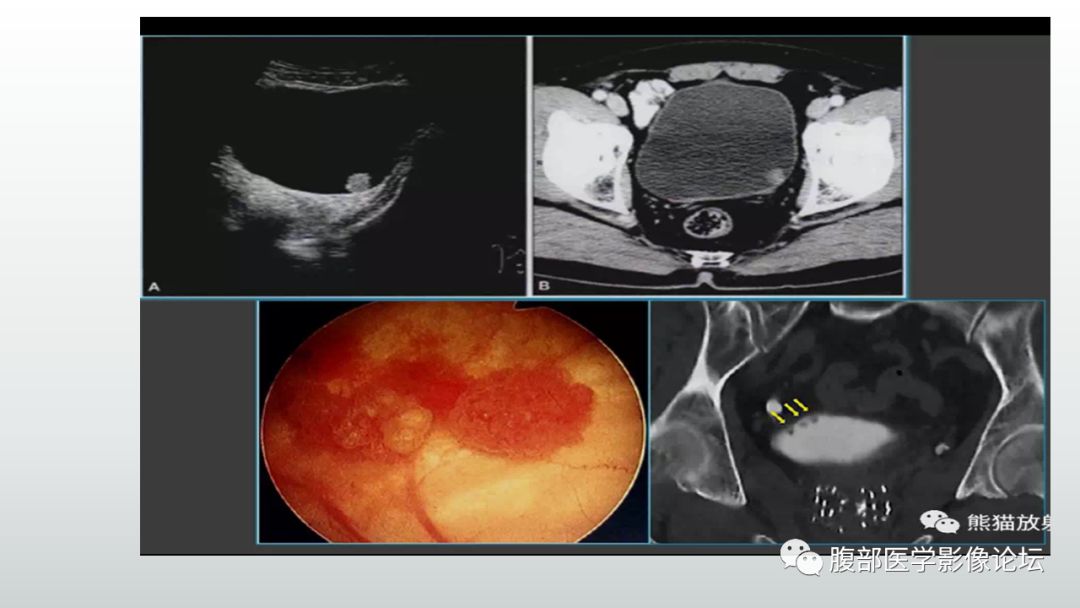

镜检示右侧壁菜花状肿瘤彩超提示膀胱内实质性占位病变,考虑膀胱肿瘤

85岁女性,血尿,膀胱刺激症状,检查发现膀胱巨大肿瘤,10. - 抖音